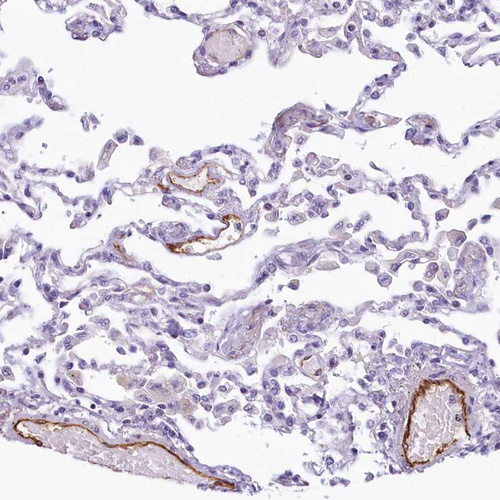

Immunohistochemical staining of human endometrium shows strong cytoplasmic positivity in endothelial cells.